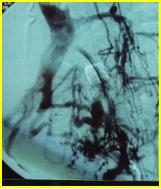

髂股静脉血栓大部分溶解,显示左髂静脉受压情况(Cockett综合征),见图5

图5